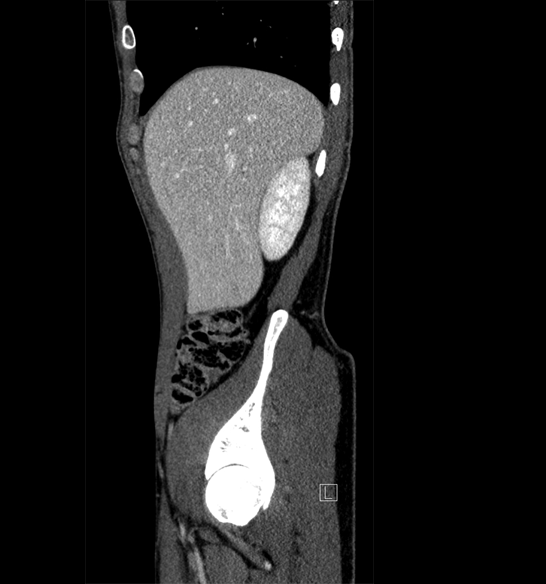

Body

Covers abdominal CT anatomy.